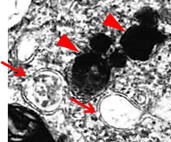

さらにgadマウスの延髄薄束核を電子顕微鏡で観察したところ、NADでみられるdense body(矢尻)に加え、二重膜をもったオートファゴソーム様の構造物(矢印)も見出しました。(図2)

図2)gad mouseのhomoの延髄薄束核の電顕像。

電子密度の高いdense body(矢尻)とオートファゴソーム様の構造物(矢印)がみられる。